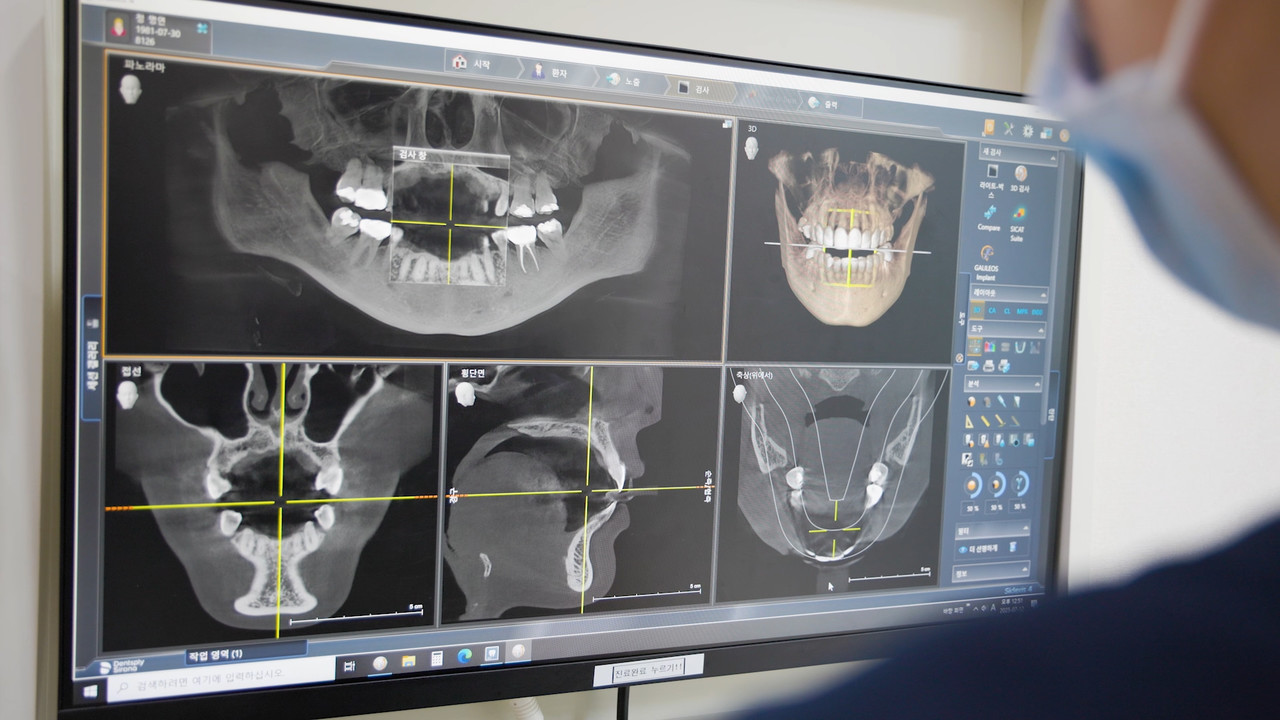

셋. 필요 시, 최종 확인을 위한

'3D-CT 입체 분석'

통증의 원인이 치아 내부의 신경이나 뼈와 관련이 있다고 의심될 때, 3D-CT를 통해 치아 뿌리 상태를 3차원으로 확인합니다. 신경치료의 성공률을 높이고, 발치 여부를 결정의 중요한 근거가 됩니다.

셋. 필요시, 최종 확인을 위한